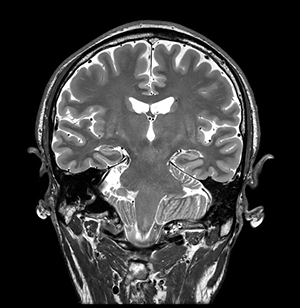

k空間データ全体に対して直接ディープラーニングアルゴリズムを適用し再構成する事でノイズ低減,画像の尖鋭度向上,トランケーションアーチファクトが低減する。従来の画像再構成とAIR™ Recon DLによる画像再構成との2つの比較画像を以下に添付する。

(2) 画質が向上し撮像時間が短縮

従来の画像再構成(撮像時間:4分13秒) |

AIR™ Recon DLによる画像再構成(撮像時間:1分47秒) |